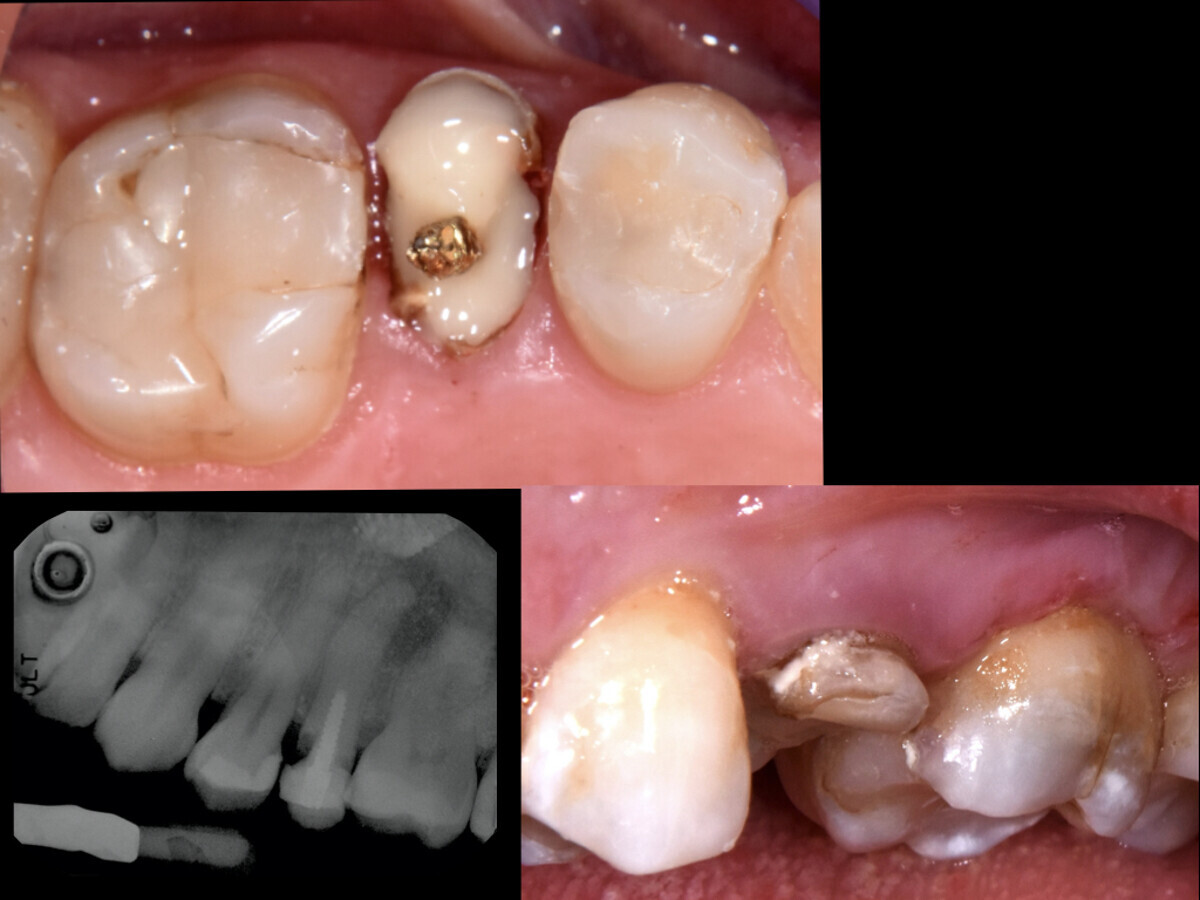

Fig. 1: Restauración de composite antigua, fractura de la cúspide y absceso periapical en la pieza 25 con inflamación de la mucosa alveolar debida al absceso (véanse los hallazgos en la radiografía intraoral).

Diagnóstico: estado tras el tratamiento postendodóntico con poste de metal. Absceso periapical y fractura de la cúspide en la pieza 25 con inflamación de la mucosa alveolar debida a un absceso en la región afectada (Fig. 1).

Comparación de la situación antes y después: las fases más complejas y que requirieron más tiempo del tratamiento fueron la restauración del efecto de cincho protésico adecuado y la reconstrucción adhesiva del muñón. De esta forma se cementó una corona de resina de manera provisional pero estable, y con ello se restableció la función del resto de la raíz de la pieza 25 durante la masticación, lo que ya no sucedía anteriormente (véase Fig. 1 y 4).

Fig. 4: Cementación convencional de la prótesis provisional durante cuatro meses (Provicol QM, VOCO), que permanece incorporada hasta la cicatrización completa del tejido. Después, se planifica una restauración definitiva con una corona de disilicato de litio.